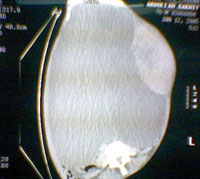

استئصال كيس مائي ضخم من بطن مريض بجازان

نجح فريق طبي بقسم الجراحة العامة بمستشفى الملك فهد المركزي بجازان مكون من استشاري جراحة عامة ورئيس أقسام الجراحة بجازان الدكتور عبد الرحمن العريشي واستشاري الجراحة الدكتور محمد شهيد خان في إجراء عملية جراحية لمريض في العقد الثامن من عمره يعاني من تورم كبير في البطن حيث أُجريت له عملية جراحية وتم استئصال كيس مائي كبير جداً من بطن المريض.. وأوضح الدكتور عريشي بأن المريض كان يعاني من الورم منذ طفولته في السنة الثانية من عمره.. وراجع مستشفى الملك فهد المركزي.. وكان يشكو من ألم وتورم في البطن ويعاني من ضيق التنفس وضعف شديد في وظائف الكلى وتم عمل الفحوصات اللازمة له، وقد أظهرت الأشعة المقطعية للبطن وجود كيس مائي كبير (كيس كلابي)، وأضاف العريشي بأنه تم إجراء عملية للمريض حيث تمت إزالة كيس مائي يزن 37 لتراً يحتوي على سوائل وأكياس تابعة، مشيراً إلى أن العملية تمت بنجاح ولله الحمد.. وتم تحويل المريض إلى وحدة العناية المركزة لمتابعة حالته ومراقبتها, وأضاف العريشي بأن الكيس يُعتبر أكبر كيس مائي يتم استئصاله على مستوى العالم من حيث الوزن.. وتم تقديم هذا الحدث لتوثيقه بكتاب غينيس للأرقام القياسية العالمية.